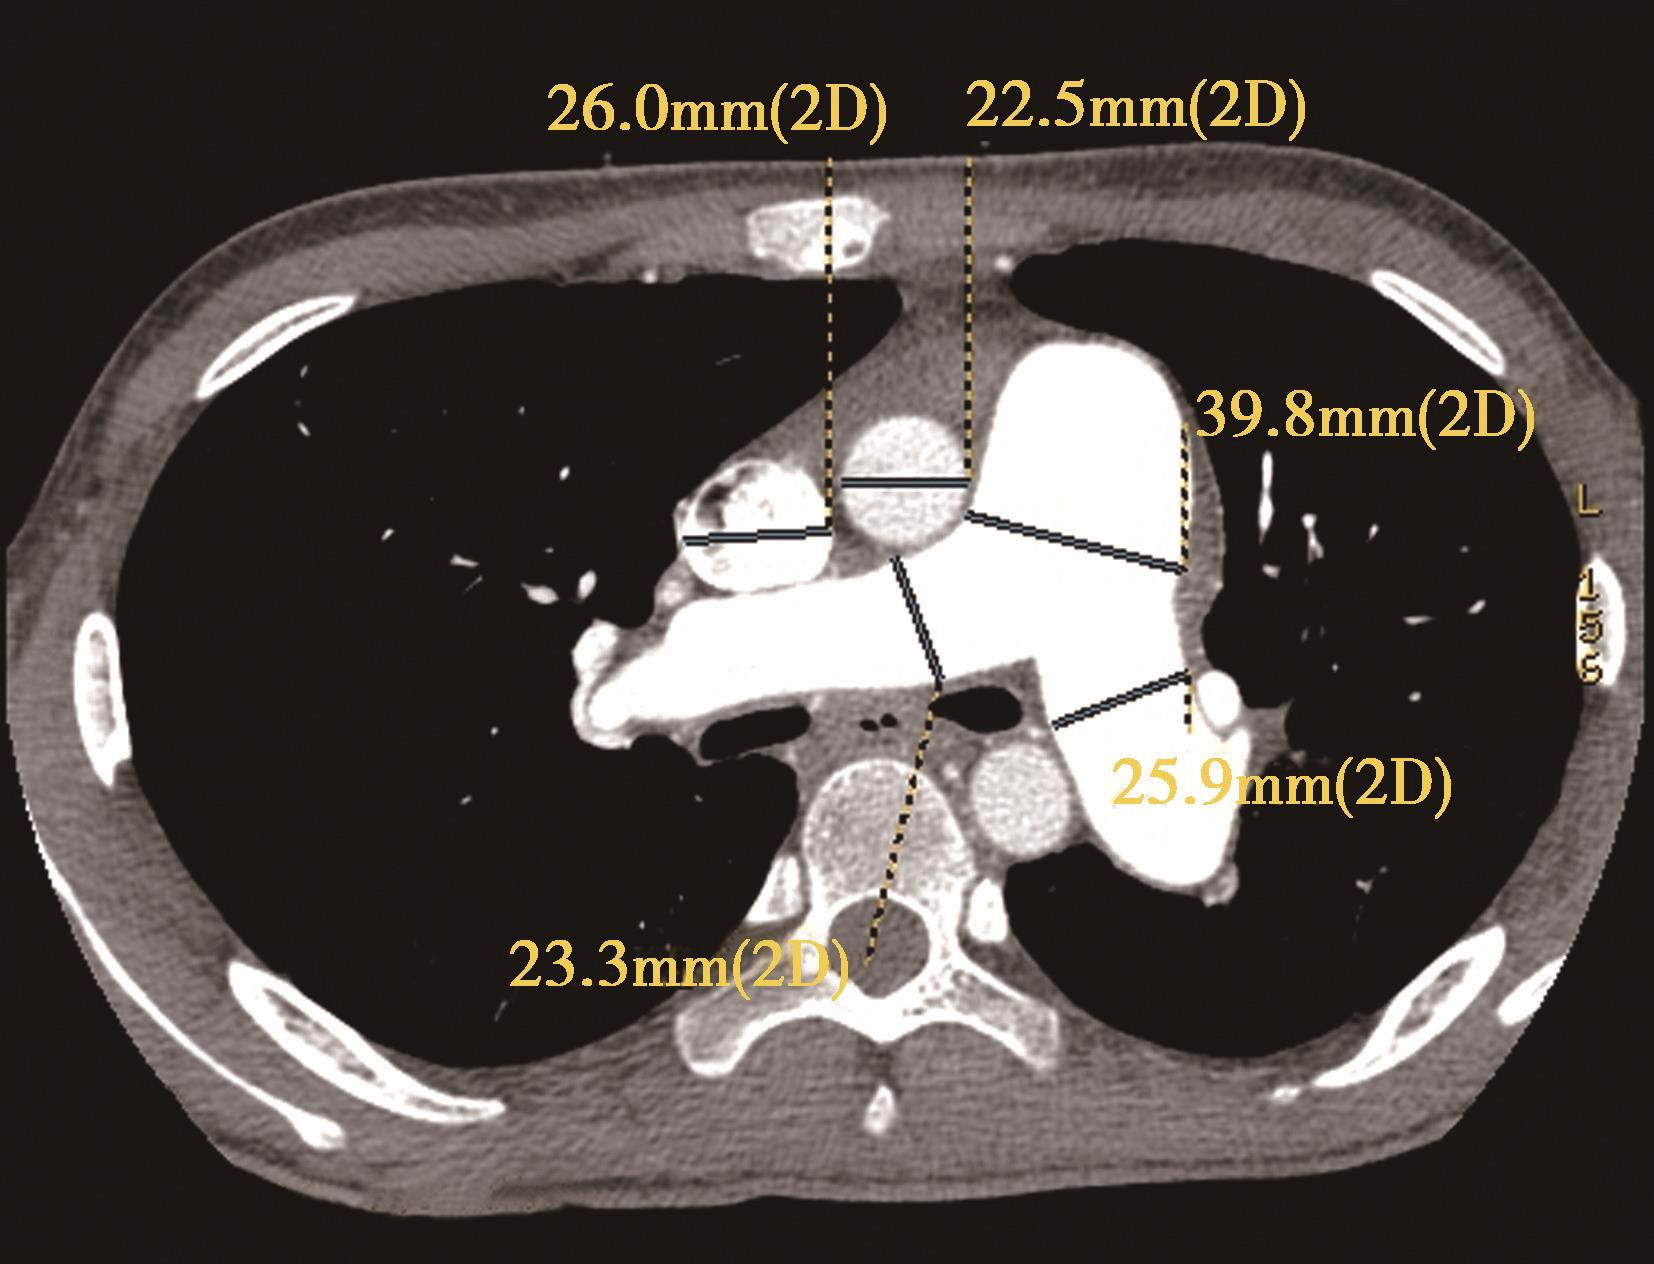

横断像心室最大层面测量左右心室最大横径(图8-3-10),正常心脏右心室横径:左心室横径<1,(a∶b<1),室间隔居中(红色↑)。右心室增大,右心室横径:左心室横径>1,(a∶b>1),室间隔凸向左心室(红色↑)。

图8-3-10 横断图像

A.正常心脏,a∶b<1; B.右心室增大,a∶b>1

3.CTPA对右心功能不全(RVD)的定性及定量诊断标准目前尚无定论,较为公认的定性诊断方法是右心室增大,即右心室最大短轴横径(RVd)超过左心室最大短轴横径(LVd)。文献报道横切位图像上心脏的量化测量指标,RVd和LVd,特别是RVd/LVd,与肺栓塞的严重程度和死亡呈正相关(RVd,RVd/LVd)或负相关(LVd)。在对25例肺栓塞和14例大面积肺栓塞患者的研究中,Contractor等和Lim等发现以超声心动图为参考标准,CTPA对RVD(诊断标准为RVd/LVd>1和/或室间隔移位)的诊断敏感性为78%~92%,特异性为100%,阳性预测值为100%。Araoz等的研究认为,与右心室大小正常的肺栓塞患者相比,RVd/LVd>1的肺栓塞患者进入重症监护室的危险度高3.6倍。多项研究也认为RVd/LVd>1.5提示肺栓塞患者的病情严重。Collomb等的研究认为,通过分析CTPA显示的肺动脉树的阻塞程度、左心室最大短轴直径、右心室/左心室最大短轴直径比和主肺动脉直径,可以对肺栓塞患者血流动力学损害的严重程度进行评价。因此,RVd/LVd在肺栓塞患者的病情评价方面有着非常重要的临床意义。此外研究显示肺动脉高压患者,脊柱室间隔夹角与右心功能参数具有显著相关性,提示该角在评价肺动脉高压患者右心功能具有一定价值。

Cecilia研究报告,CT右/左心室径比值(dimensional ratio)>1.0评价右心室功能不全,是急性肺栓塞院内死亡及临床恶化的独立预测因子(HR 3.5,95%CI 1.6~7.7; P =0.002)。 急性肺栓塞右心室正常a∶b<1,无事件转归的阴性预测值为100%[95%可信区(CI)下限为94.5%]。